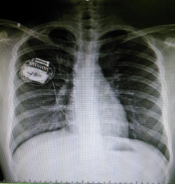

1. Spinal nerve electrostimulation therapy

Spinal nerve electrostimulation therapy is to appropriately stimulate the nerve area producing pain by small electric pulse, feedback adjust nerve conduction substances, and produce tolerable numbness to replace pain, so as to play the role of relieving pain. It is effective for treating herpes zoster, and has the following advantages: